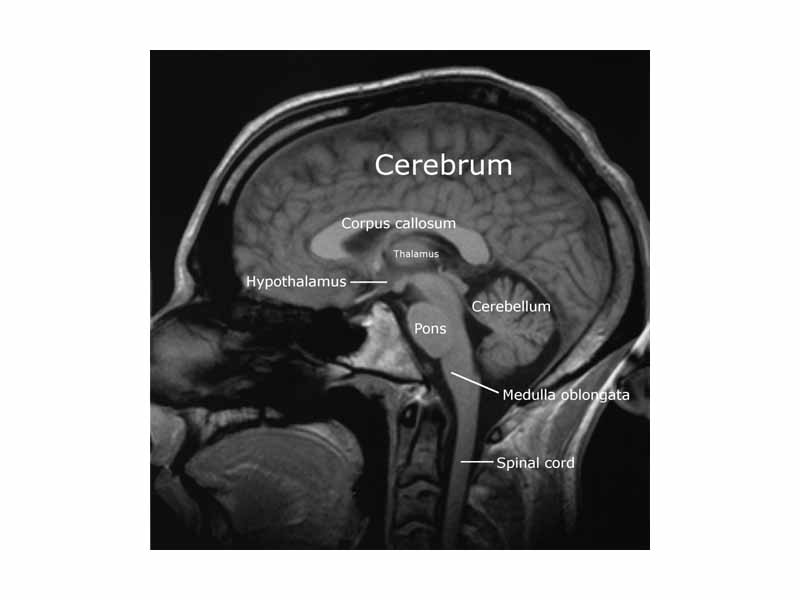

Sagittal slice from a MRI scan of a human brain. See an animated sequence of slices.